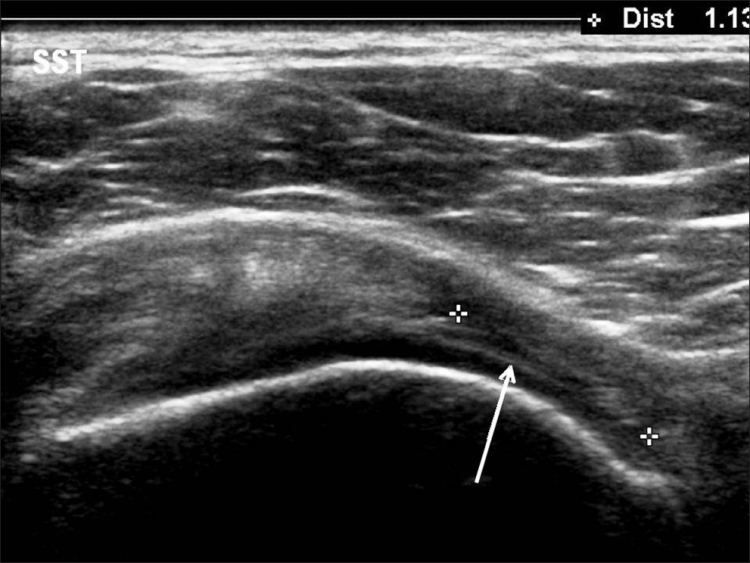

Los desgarros del manguito de los rotadores son la patología más común que se encuentra en los exámenes de ultrasonido del hombro.[7] La incidencia de lágrimas aumenta con la edad. Los desgarros de tendones se pueden clasificar de acuerdo con el grado de falla de la fibra, que van desde desgarros completos [Figura 7], desgarros de espesor total [Figuras 8, 9], desgarros de espesor parcial [Figuras 10-12] y desgarros intrasustancia [Figura 13 ]. Un desgarro agudo suele ir acompañado de derrame articular o bursal [Figura 12]. [7-9] La ausencia de derrame generalmente se relaciona con desgarros crónicos.[9] En un metanálisis sobre la precisión de la resonancia magnética, la artrografía por resonancia magnética y la ecografía en el diagnóstico de desgarros del manguito de los rotadores, la ecografía ofreció una alta sensibilidad y especificidad para la evaluación de los desgarros del manguito de los rotadores de espesor total (92,3 y 94,4 %, respectivamente) con 85,1 % y 92 %, respectivamente para todas las lágrimas.[7] El desgarro de espesor parcial aparece como un defecto o hendidura hipoecogénica en el tendón, afectando solo una parte de su espesor, mientras que un desgarro de espesor total se extiende desde la bolsa hasta la superficie articular del tendón. Un desgarro completo es un desgarro de espesor completo que afecta todo el ancho del tendón. El tendón se retrae medialmente, y la cantidad de retracción depende de la edad del desgarro. En las roturas crónicas, el tendón desaparece por debajo del arco coracoacromial, dejando la cabeza humeral descubierta por el supraespinoso, el denominado signo de la "cabeza desnuda". Los hallazgos de la ecografía incluyen la falta de visualización del tendón y la hernia del músculo deltoides. Los desgarros intrasustancia permanecen localizados en el tendón sin afectar sus márgenes. Los desgarros intrasustancia y de espesor parcial pueden ser difíciles de diferenciar de la tendinopatía focal.

Las patologías no relacionadas con desgarros del manguito rotador que se encuentran con más frecuencia son la tendinosis del manguito rotador [Figura 14], la tendinitis calcificante del manguito rotador [Figura 15] y el pinzamiento del tendón subacromial [Figura 16]. Vale la pena señalar que, en tales casos, se pueden desarrollar desgarros debido a la debilidad del tendón [Tabla 2].[79] La tendinosis o tendinopatía del manguito de los rotadores se presenta como inflamación del tendón con una ecotextura hipoecoica heterogénea del tendón. Las calcificaciones del manguito de los rotadores aparecen como focos hiperecogénicos, ya sea con una sombra posterior bien definida (Tipo I) o con una sombra tenue (Tipo II) o ausente (Tipo III). El Tipo I corresponde a la fase formativa y los Tipos II y III a la fase de reabsorción, en la que cambian a depósitos de calcio semi o totalmente líquidos. En el pinzamiento subacromial, el tendón no se desliza en el espacio subacromial durante la abducción y la elevación anterior del brazo.